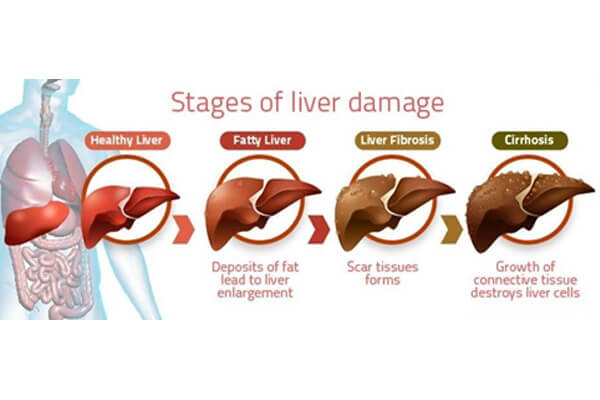

Given our lifestyle, there are many factors that lead to MASLD. According to recent studies from the Indian subcontinent, the prevalence of Metabolic dysfunction-Associated Steatotic Liver Disease in India is seen among 9–32% in the general population. As per the studies undertaken, it has been established that hypertension, type II diabetes, smoking, obesity, and dyslipidaemia are significantly associated with MASLD.

Given our lifestyle, there are many factors that lead to MASLD. According to recent studies from the Indian subcontinent, the prevalence of Metabolic dysfunction-Associated Steatotic Liver Disease in India is seen among 9–32% in the general population. As per the studies undertaken, it has been established that hypertension, type II diabetes, smoking, obesity, and dyslipidaemia are significantly associated with MASLD.